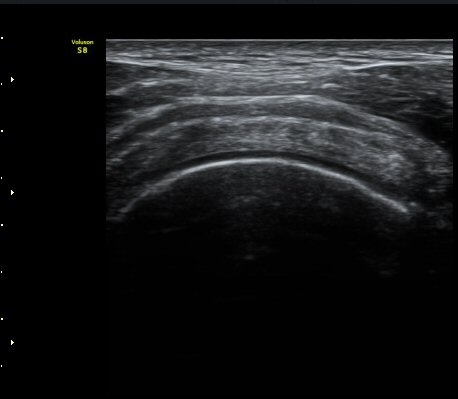

ÀÌµÎ¹Ú±Ù°Ç È¾´Ü¸é°Ë»ç¿¡¼­ ƯÀÌ ¼Ò°ßÀ» º¸ÀÌÁö ¾ÊÀ½(»çÁø 1, 2).